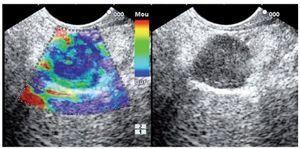

Category 1 is for a homogenous low elastography area (soft, green) and corresponds to the normal pancreas tissue (Figure 1). For images classified as category 2 (Figure 2) there is heterogeneity of the elastography but in the soft tissue range (green, yellow, and red) and corresponds to fibrosis. Category 3 (Figure 3) is for elastography images which is largely blue (hard) with minimal heterogeneity and corresponds to a small, early (less than 25 mm) pancreatic adenocarcinoma. In tumors assigned Category 4 (Figure 4) there exists an hypoechoic region with green appearance in the center of the tumor, surrounded by blue or harder tissue and corresponds to a hypervascular lesion, such as a neuroendocrine tumor or small pancreatic metastasis. Finally, Category 5 (Figure 5) is assigned to lesions which are largely blue on SE but with heterogeneity of softer tissue colors (green, red), representing necrosis, and is seen in advanced pancreatic adenocarcinoma. The elasticity of soft tissues depends to a large extent on their molecular composition (fat, collagen, etc.), as well as on the microscopic and macroscopic structural organization of these blocks. In the normal pancreas, for example, the glandular structure may be firmer than the surrounding connective tissue, which in turn is firmer than the subcutaneous fat. SE allows the hardness or stiffness of biological tissues to be estimated and imaged using conventional ultrasound instruments with modified software. It is known that certain pathologic conditions, such as malignant tumors, often manifest themselves as changes in the mechanical properties of tissue. We believe that the elastic properties of benign lesions are fairly uniform, such as throughout a benign tumor. Cancerous tumors, on the other hand, grow in a very disorganized way. Therefore, within a given malignant tumor, the elastic properties of one area of a tumor may be significantly different from those in another area. The concept relating to the measurement of these tissue changes is an extension of the basic principles associated with traditional medical ultrasonic imaging. The principle is based upon the fact that tissues are deformed slightly when a small displacement is externally applied

Figure 3. Category 3, images that are largely blue (indicative of hard tissue) with minimal or no heterogeneity.

Figure 4. Category 4, green appearance for the central small area surrounded by blue (or hard) tissue, which corresponds to a hypervascular lesion, such as a neuroendocrine tumor or small pancreatic metastasis.